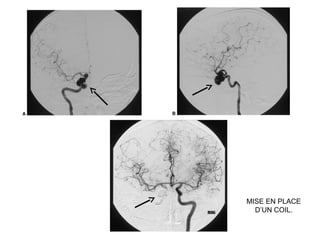

CT scans des sinus en coupe axiale (A) et coronale (B), avec injection de contraste :

Anévrysme trilobé du segment intra caverneux de l’ artère carotide interne droite

avec érosion paroi externe sinus sphénoidal.

MISE EN PLACE

D’UN COIL.

LES COILS EN NEURORADIOLOGIE

INTERVENTIONNELLE.

Les coils sont des spires métalliques utilisées comme matériel d’occlusion

endovasculaire.

Les coils permettent le remplissage endovasculaire d’un compartiment vasculaire

relativement large (anévrysme intracrânien, sinus veineux dural, artère

cérébrale). Jusqu’au début des années 80, cela ne pouvait se faire qu’à l’aide de

ballonnets largables dont l’un des inconvénients majeurs était le dégonflage

précoce. Cet inconvénient n’existe pas pour les coils du fait de leur

structure métallique.

Tous les coils sont faits d’une tresse de platine. Le platine est en effet un métal

noble qui ne se corrode pas dans le courant sanguin et qui, par ailleurs, ne

détermine pas d’allergie.

Ces coils ont des formes diverses : hélicoïdales, sphériques, droites. Les coils

hélicoïdaux, qui sont probablement les plus utilisés, sont définis par le diamètre

de la spire (de 2 à 20 mm) et par leur longueur totale (de 10 à 500 mm).

Le principe est d’introduire un microcathéter à l’intérieur du sac anévrysmal

afin d’y dérouler des spires de diamètres progressivement décroissants.

On réalise ainsi une pelote métallique que l’on densifie jusqu’à ce que le

produit de contraste n’opacifie plus l’anévrysme sur l’artériographie de

contrôle.

Le nombre moyen de coils implantés par anévrysme est de 3,5.

coût: environ 700 €

Schémas d’une embolisation d’anévrysme à l’aide de coils.

A. Cathétérisme du sac.

B. Vue finale après détachement du coil et retrait du microcathéter.

A B